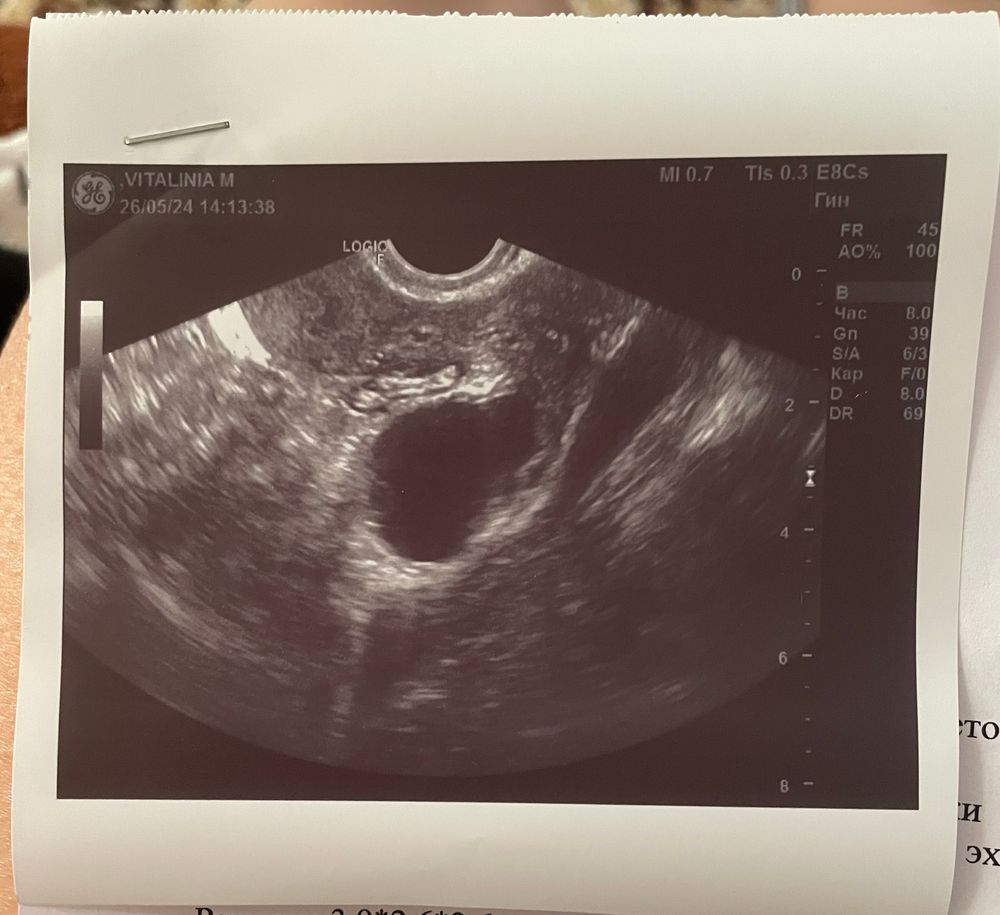

Узи и переживания...

Изображение

Девочки, как то странно, что не написали даже размер ПЯ, по мес срок 6+3, но О была на 21 ДЦ, поэтому неудивительно что не видно ещё эмбриона, а так я не понимаю, все